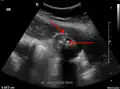

Right upper quadrant abdominal ultrasound is most commonly used to diagnose cholecystitis.[1][26][27] Ultrasound findings suggestive of acute cholecystitis include gallstones, pericholecystic fluid (fluid surrounding the gallbladder), gallbladder wall thickening (wall thickness over 3 mm),[28] dilation of the bile duct, and sonographic Murphy's sign.[13] Given its higher sensitivity, hepatic iminodiacetic acid (HIDA) scan can be used if ultrasound is not diagnostic.[13][14] CT scan may also be used if complications such as perforation or gangrene are suspected.[14]

Acute cholecystitis as seen on ultrasound. The closed arrow points to gallbladder wall thickening. Open arrow points to stones in the GB